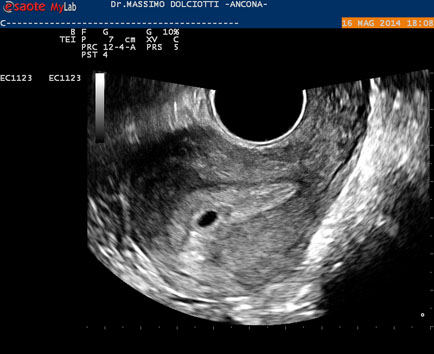

Data inserimento: 19 /05/2014Ecografia del: 16/05/2014 Strumento: Esaote MyLab 50 Gold - Responsabile Linea Cardio Esaote Regione Marche Dr. Franco Fabi Sonda: Endocavitaria Multifrequenza 4-8 MHz Età Paziente: F 27 anni Motivazione dell'esame: amenorrea. Beta HCG = 1.459 mUI/ml. Commento all'esame: le immagini ed il video documentano utero retroverso, con endometrio ispessito e presenza del sacco gestazionale delle dimensioni di 7,6 x 7,2 mm. All'ovaio destro presenza di corpo luteo gravidico con vascolarizzazione aumentata. Conclusioni: gravidanza alla quarta settimana di gestazione (Pregnancy at the fourth week of gestation). Potete esprimere le vostre osservazioni e commenti sul BLOG. Presentazione: Dr. Massimo Dolciotti - Ancona Elaborazione digitale: Andrea Dini - Ancona